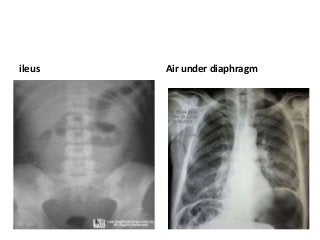

Plain abdominal radiographs

• are typically normal in patients with mild diverticulitis,

• but in the setting of severe disease, there may be an

ileus pattern, or, if obstruction is present, proximal

bowel dilation. A large abscess may be associated with

an air-fluid level on upright films. If there is perforation

into the retroperitoneal space, the psoas shadow may

be obliterated due to air diffusing along the psoas

muscle. Free air under the diaphragm may be seen on

upright films in the setting of intraperitoneal

perforation, especially if there is feculent peritonitis.

ileus Air under diaphragm